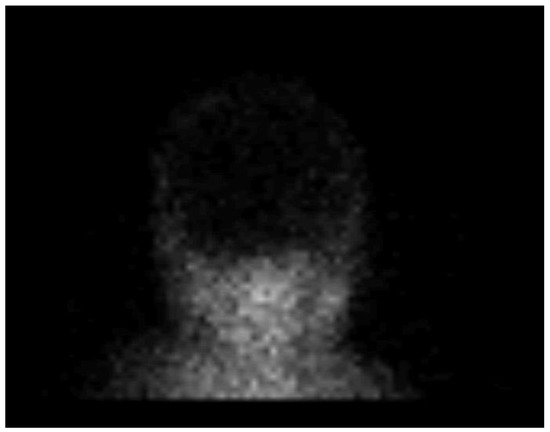

CEUS was performed as an ancillary imaging test for the confirmation of brain death. Before the examination, the details of the examination and the risks for the patient were explained to the child’s guardian. Written informed consent was obtained from the child’s guardian to perform the brain CEUS scan. The examination was performed by a paediatric radiologist with 2 years of subspecialty experience in paediatric brain imaging and 4 years of experience in performing CEUS examinations. For the examination, a Mindray M9 ultrasound scanner with a 1.4–5.1 MHz convex ultrasound transducer was used (Mindray, Shenzhen, China). SonoVue (Bracco, Milan, Italy) was used as the contrast agent. The anterior fontanelle was used as the acoustic window to scan the brain in the coronal and sagittal planes. Firstly, pre-contrast grey-scale imaging was performed to optimise the image. After that, a contrast-specific imaging mode and a low dynamic mechanical index (MI) of 0.06–0.07 was used for the scanning during the CEUS examination. To enable the simultaneous attachment of the US contrast agent and saline to the line, to avoid any delays in flushing the line with a saline flush, a three-way stopcock was connected to the existing peripheral intravenous line. At the start of the examination, 0.3 mL of US contrast agent, followed by a saline flush, was intravenously applied through a peripheral line. Only one bolus of US contrast agent was administered during the examination. For the first 60 s after the contrast administration, a continuous cine clip was obtained in the coronal plane at the level of the third ventricle, including the frontal horns of the lateral ventricles and heads of the caudate nuclei bilaterally. After that, intermittent images were obtained during the next 10 min in order to assess brain perfusion and avoid excessive contrast microbubble destruction from continuous imaging. The CEUS examination showed enhancement of the extracranial vessels and a lack of enhancement of the intracranial vessels (Figure 2). Only a scant amount of contrast microbubbles was observed within the left middle cerebral artery and pericallosal artery during the examination (Figure 3). After 10 min, we observed complete microbubble clearance and finished with the examination. The brain CEUS examination was performed in a paediatric intensive care unit at the bedside, and the whole procedure, including preparation, lasted approximately 15 min. No adverse effects were observed after the intravenous application of US contrast agent.

CEUS allows the observation of organ perfusion over a longer period of time, which makes it a great tool for the evaluation of organ perfusion. It takes up to 15 min for the contrast microbubbles to be metabolised and disappear from the vessels [16,17]. In our case, we observed the brain for 10 min. During this time, we did not observe any constant flow through any of the intracranial arteries. However, during the observation period, a scant of contrast microbubbles were observed within the left middle cerebral artery and pericallosal artery for a few seconds. It is important to note that, although we observed scant contrast microbubbles within the intracranial arteries, the perfusion scintigraphy showed no accumulation of the radionuclides in the brain. Therefore, we can assume that scant microbubbles within the intracranial arteries can be a finding on CEUS during the test for brain death confirmation and that this finding does not exclude a brain death diagnosis. However, as this was the first such examination that we performed and no other similar reports exist in the literature, we cannot make any final conclusions. In the aforementioned case by Hwang et al., they reported “near absent perfusion of the intracranial vessels”, which is similar to our case [5]. Further research will be needed to better delineate the extent and context of scant microbubbles within intracranial arteries for this kind of test.

Figure 3. Sagittal contrast-enhanced ultrasound image of a 1-year-old infant’s brain obtained 101 s after contrast administration. The image demonstrates a scant amount of contrast microbubbles within the pericallosal artery and its branch (arrows) and no brain perfusion.